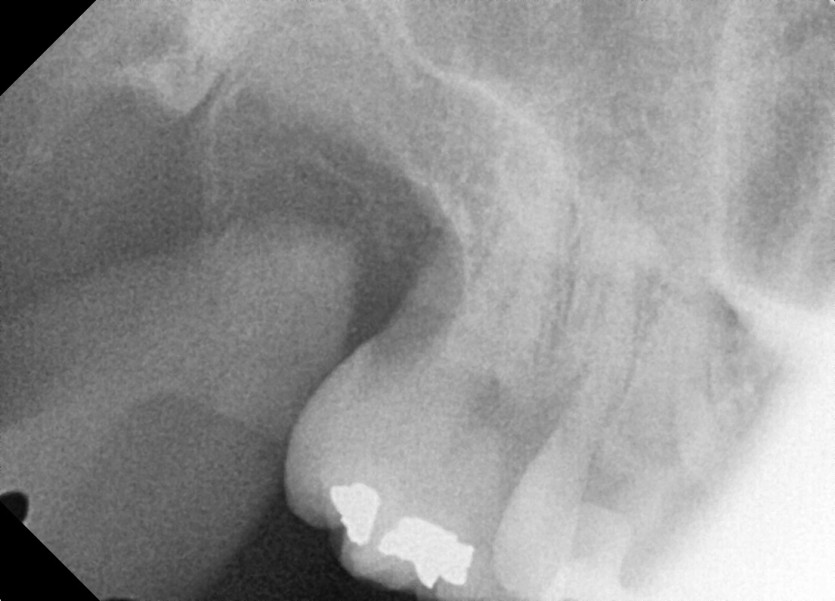

#18,28,38,48 사랑니 발치

구강 외과 전문의가 당일 발치했습니다.